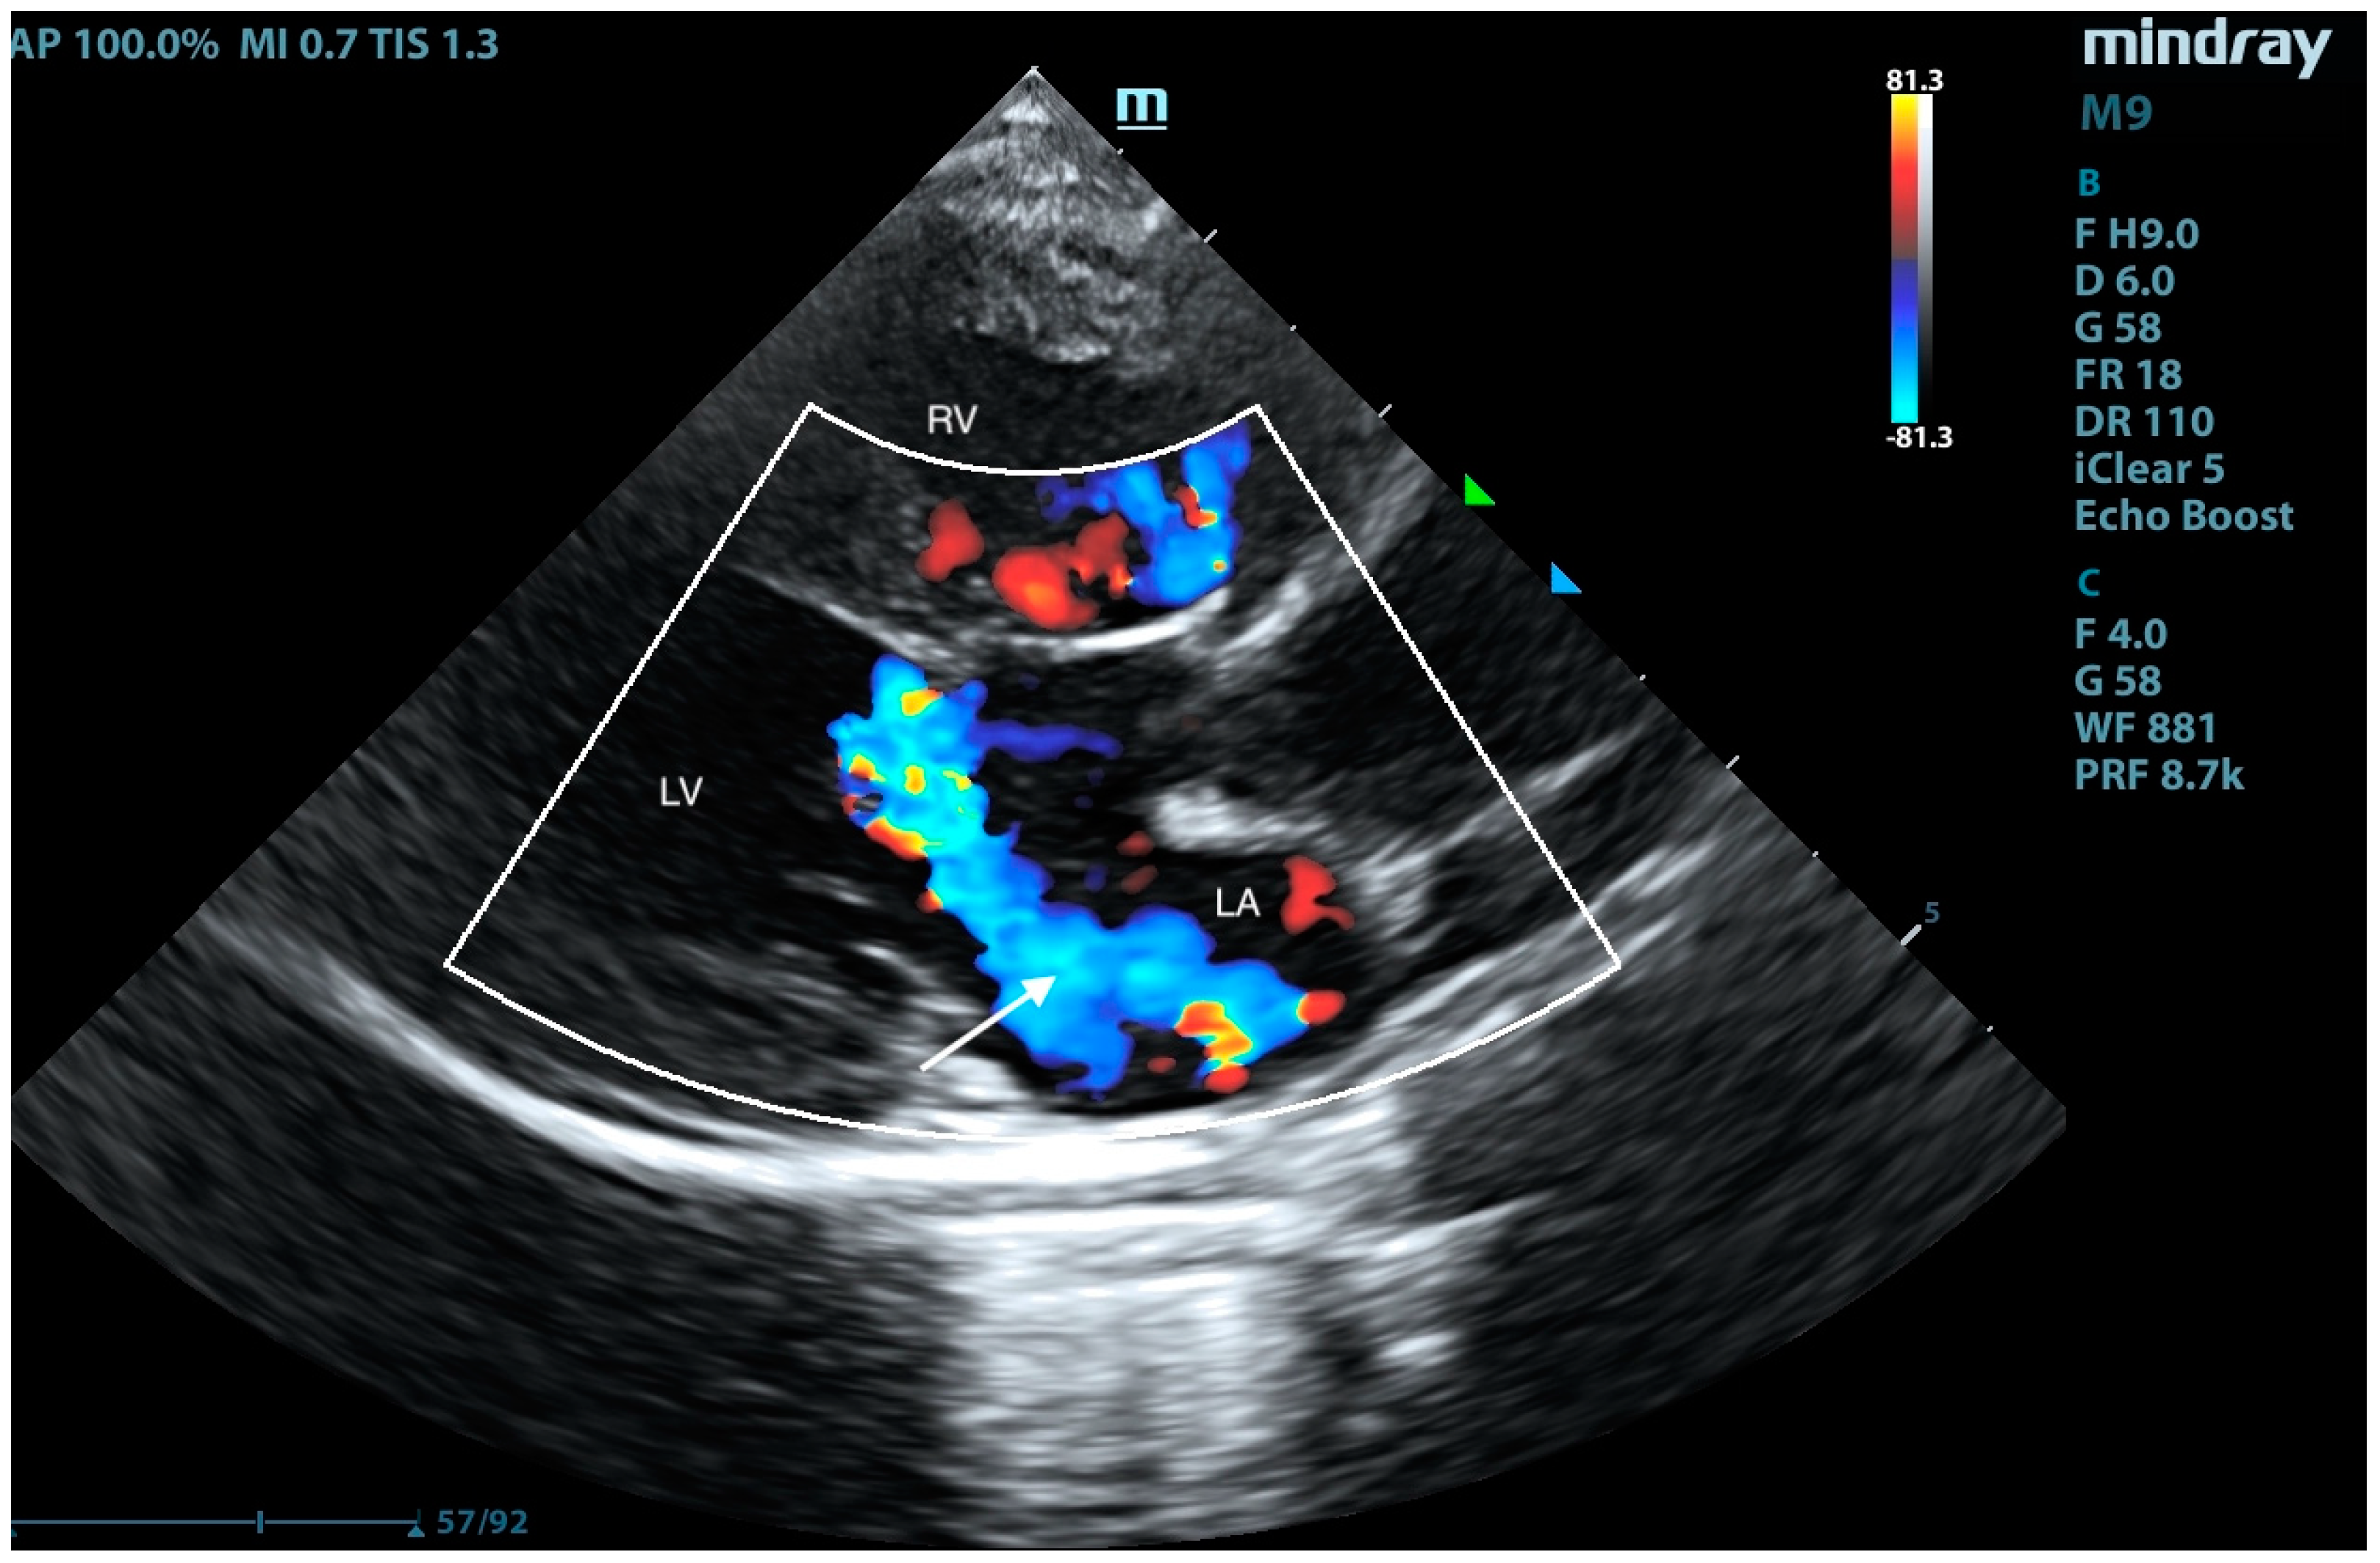

2. Case Presentation